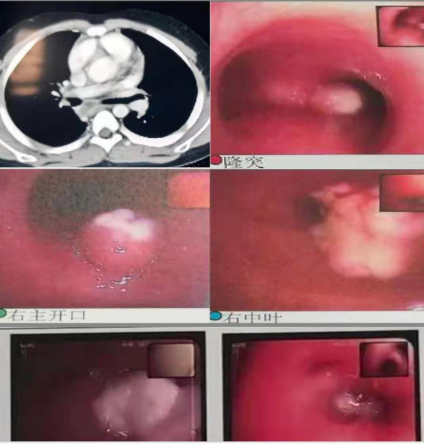

以下为呼吸专业典型病例分享:

图片2:气管狭窄后电切、球囊扩张、二氧化碳冷冻治疗

图片5:气管内膜结核及重症支原体肺炎所致气道阻塞、塑性支气管束